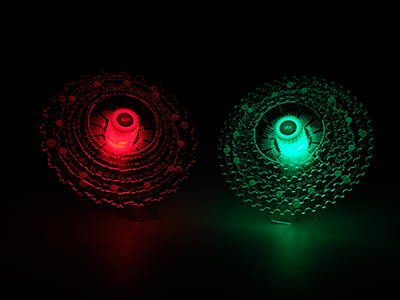

Having worked in the design and digital sectors for all of my career, it has always been a dream to create and launch my own product. However it took a twist of fate to accelerate the process. Not on one of those ‘epic rides’ but on a regular Saturday morning club ride I found myself ending up in A&E with cracked ribs and yes the dreaded broken clavicle! This meant long periods of zero bike time and more time focusing on completing the prototypes. They say every cloud has a silver lining and certainly that Saturday morning ride sent me off on a completely different journey and certainly one I couldn’t record on the Garmin or post to Strava!

pg-pic xray-img